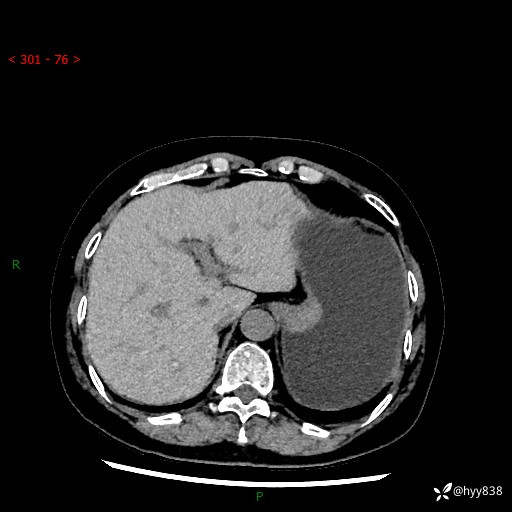

胃CT平扫+增强(动脉期+静脉期)

三期CT值:46hu 58hu 75hu